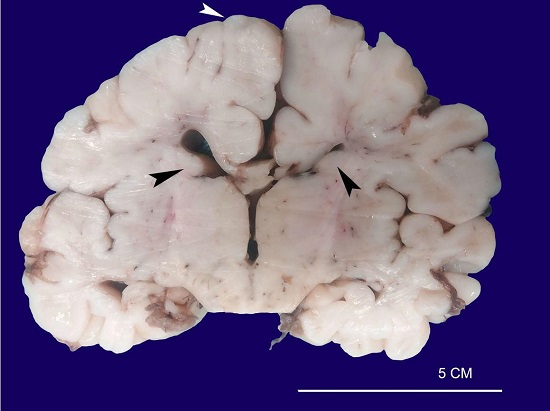

The brain weighed 110g (average brain weight adapted for age and birth weight: 337 ± 91g). The cut surface revealed multiple glioneuronal hamartomas (cortical tubers) and subependymal nodules along the walls of the lateral ventricle (Figure 3).

Histologically, the cortical tubers and subependymal nodules were composed by a proliferation of large and atypical neuronal and glial cells (Figure 4A, 4B). One of the subependymal lesions is represented by a subependymal giant cell tumor (SGCT), comprised of a combination of giant cells with glassy, eosinophilic cytoplasm and round nuclei with conspicuous nucleoli, interspersed with spindled cells and fibrillary elements (Figure 4C, 4D). This type of lesion is characteristic of tuberous sclerosis complex (TSC).